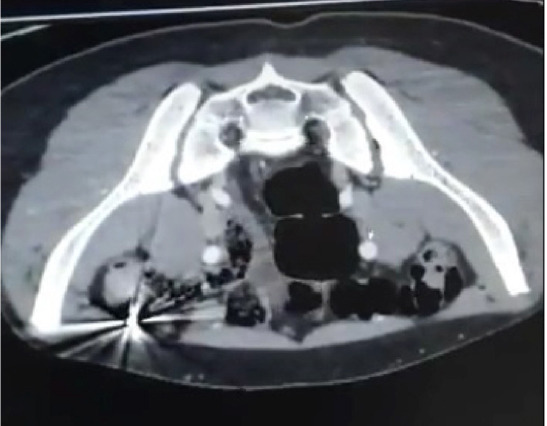

Background: This study aimed to evaluate the epidemiological data on thoracic and abdominal firearm injuries in children treated by pediatric surgeons at a pediatric trauma center.

Methods: Children hospitalized with firearm injuries from 2015 to 2022 were retrospectively analyzed. Patient demographics, affected organs, treatment, and length of hospital stay were analyzed retrospectively.

Results: The mean age of the patients was 12.43+-2.31 years; 27 (84.4%) were male and five (15.6%) were female. Bullet injuries were associated with higher severity and often required major surgical intervention, whereas pellet injuries were generally managed conservatively. For thoracic injuries, conservative management was considered effective for stable cases without immediate life-threatening complications, whereas abdominal injuries more often required invasive surgical approaches. Notably, unintentional firearm injuries were more common in younger children, whereas intentional injuries were more common in older adolescents. This age-related pattern highlights a statistically significant correlation between age and type of firearm injury (p = 0.002). Also, the majority of patients with thoracic injuries underwent minor surgeries, whereas those with abdominal injuries mostly underwent major surgeries Conclusion: Our study indicates that accidental firearm injuries are more common among younger age groups, whereas intentional firearm injuries tend to occur more frequently among older children.